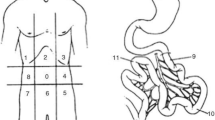

To ensure the accuracy of the surgical documentation and S-PCI, both procedures were performed by the same surgeon for a series of 25 patients in the cohort. The author calculated the S-PCI score for the 25 surgical records, which was compared with the original S-PCI score calculated by the surgeon for each case. The mean and standard deviation (SD) of the original S-PCI was 17.07 ± 9.41, and the newly calculated S-PCI was 16.23 ± 9.03. As the data were normally distributed, Student’s t-test was used to confirm a very good correlation with the original measurement. Based on these findings, the S-PCI in the remaining cases was assessed according to the original surgical reports. The PCI score developed by Sugarbaker (1998) was used to quantify both CT-PCI and S-PCI [6]. The 13 abdominal regions were assessed for tumour content and scored from 0 to 3 depending on the tumour size: 0 points indicated no visible tumour, and 1, 2 or 3 points indicated lesions with maximum diameters of 0.5, 5.0, or > 5 cm, respectively, or confluent lesions with a final score between 1 and 39. The results were analysed as continuous data and categorized into three levels (1–10, 11–20, ≥ 21 points).

All eligible patients underwent CT in the supine position with intravenous and oral contrast. Digital CT images were obtained by convention reformatted in the coronal and sagittal planes. CT-PCI was retrospectively scored using the Sugarbaker classification [20] by one of two radiology specialists (HS or JB). The CT-PCI was calculated as the sum of the numerical lesion scores assigned to the 13 abdominopelvic regions and the lesion score to the largest visible implant. Ascites (three groups) was estimated by one of two radiologists (HS or JB) concurrent with the CT-PCI evaluation. CT-ascites was evaluated qualitatively by the interpreting radiologist and assigned to one of three groups (< 500 ml, 500–1000 ml, and > 1000 ml). The CT-ascites evaluation was based on all three image projections. CPLNs were retrospectively assessed by one of two radiology specialists (SP or NOW). CPLN was defined as a pathological enlargement measuring ≥ 5 mm at the short axis in the axial plane and was scored as negative (i.e., normal) or positive (i.e., enlarged) by two radiologists (NOW and SP). The radiologists were blinded to the intraoperative data and surgical outcomes (Fig. 1).